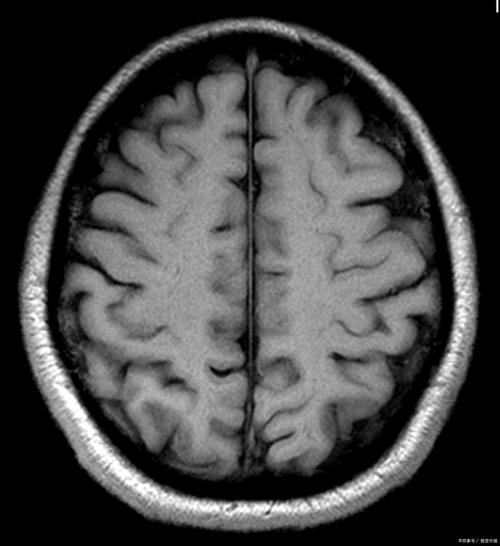

当医生在影像报告(如MRI)上看到“脑胶质增生”时,会结合孩子的具体情况进行综合判断,可能的情况从最不严重到最严重,包括: